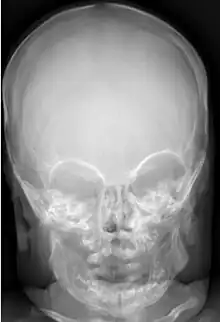

Macrocephaly is a condition in which circumference of the human head is abnormally large.[1] It may be pathological or harmless, and can be a familial genetic characteristic. People diagnosed with macrocephaly will receive further medical tests to determine whether the syndrome is accompanied by particular disorders. Those with benign or familial macrocephaly are considered to have megalencephaly.

Macrocephaly is customarily diagnosed if head circumference is greater than two standard deviations (SDs) above the mean.[11] Relative macrocephaly occurs if the measure is less than two SDs above the mean, but is disproportionately above that when ethnicity and stature are considered. Diagnosis can be determined in utero or can be determined within 18–24 months after birth in some cases where head circumference tends to stabilize in infants.[12] Diagnosis in infants includes measuring the circumference of the child's head and comparing how significant it falls above the 97.5 percentile of children similar to their demographic. If falling above the 97.5th percentile then the patient will be checked to determine whether there is any intracranial pressure present and whether or not immediate surgery is needed.[2] If immediate surgery is not needed then further testing will be done to determine whether the patient has either macrocephaly or benign macrocephaly.

Benign macrocephaly can occur without reason or be inherited by one or both parents (in which it is considered benign familial macrocephaly and is considered megalencephaly form of macrocephaly). Diagnoses for familial macrocephaly is determined by measuring the head circumference of both parents and comparing it to the child's. Benign and familial macrocephaly is not associated with neurological disorders.[2] While benign and familial macrocephaly does not result in neurological disorders, neurodevelopment will still be assessed.